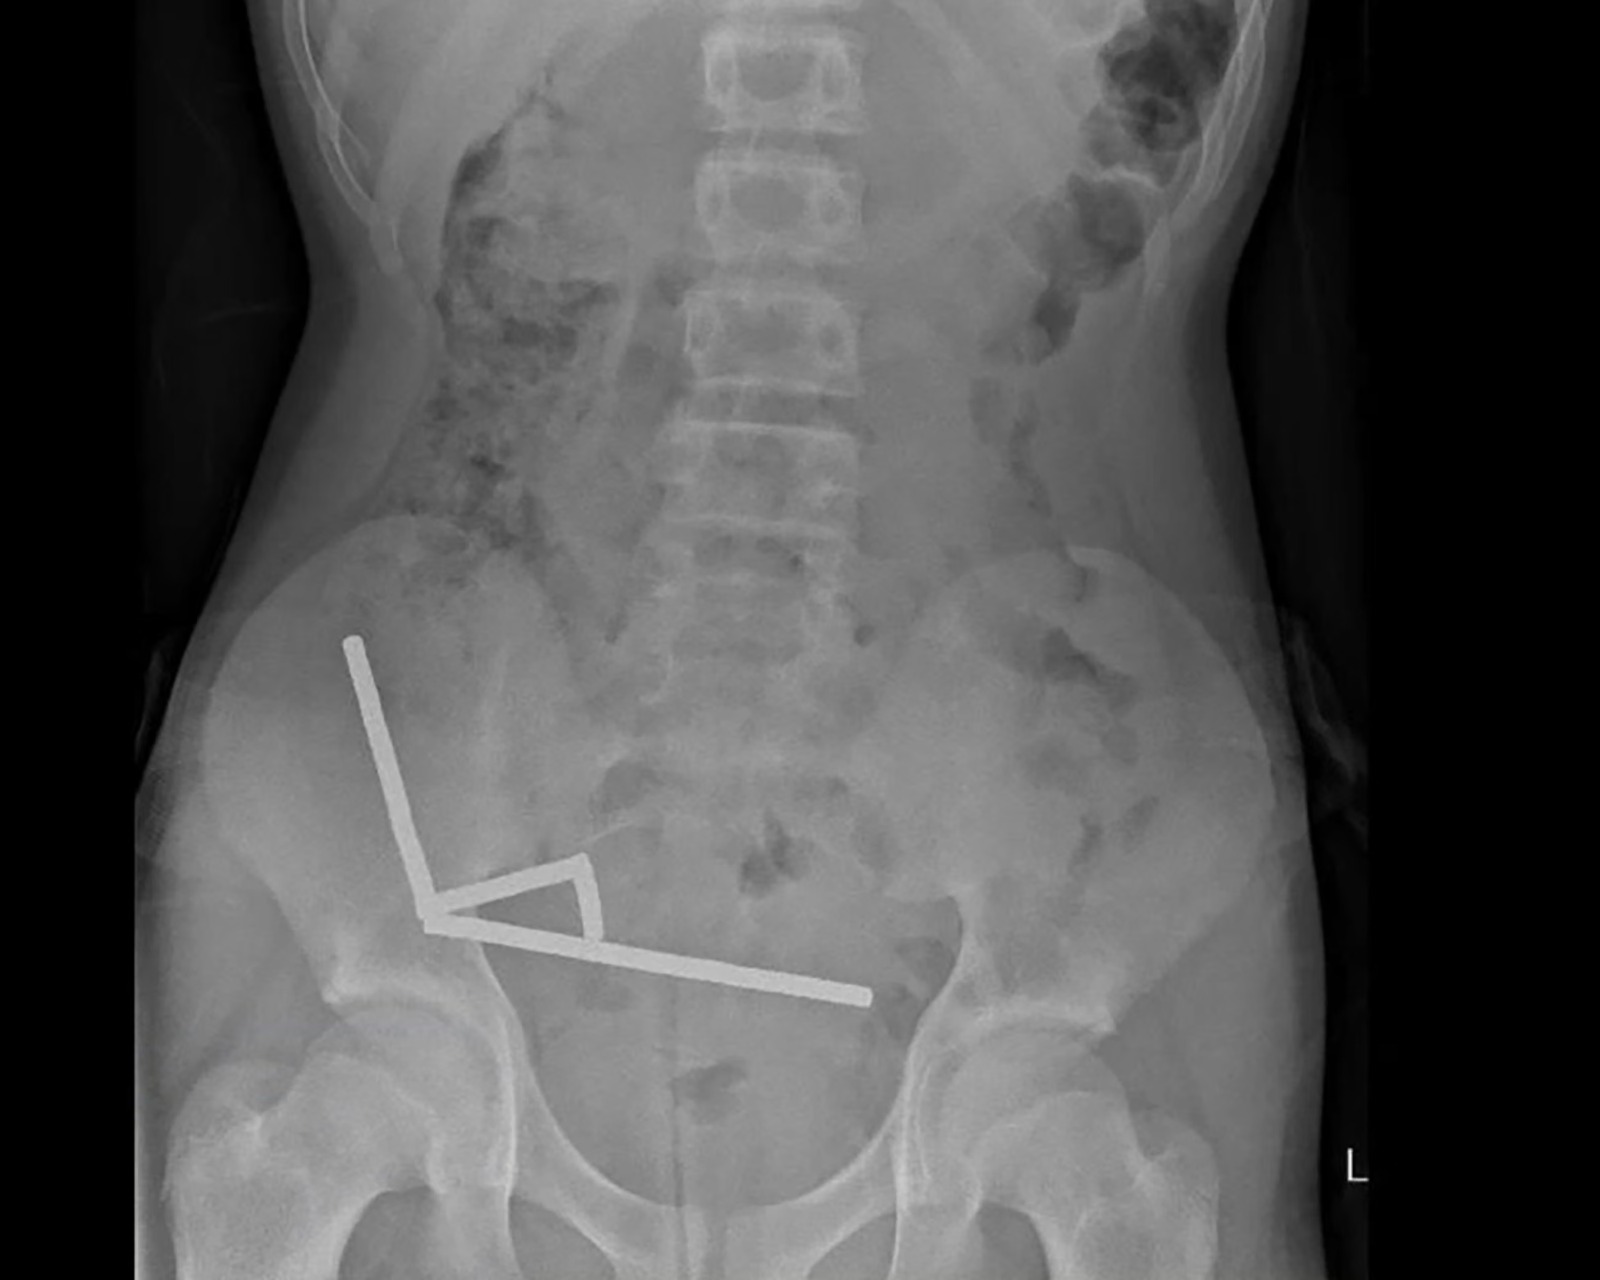

Una radiografía mostró que los imanes se habían agrupado en cuatro líneas rectas dentro de los intestinos del adolescente. «Estas parecían estar en partes separadas del intestino, adheridas entre sí debido a fuerzas magnéticas», dijeron.